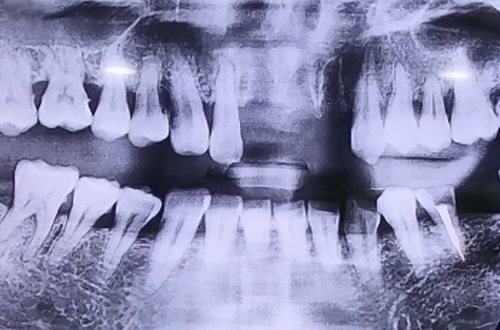

앞니 치아가 여러 개 빠진 상태의 임플란트 사례

BEFORE

넘어지면서 앞니 치아가 여러 개 빠진 환자분이십니다.

첫번 째 앞니와 두 번째 앞니, 오른쪽 앞니가 빠진 상태로 방문하셨는데

오른쪽 두 번째 치아의 경우에도 많이 흔들리고 주변의 잇몸뼈들이

으스러져 있는 상태였기 때문에 두 번째 앞니까지 발치한 뒤

임플란트 2개로 치아 4개를 동시에 만들어 주는 치료를 계획하여 진행해드렸습니다.

당일 즉시 임플란트 수술을 진행하면서 뼈이식을 통해 단단하게 보강해 준 뒤

즉시 식립을 진행하고 임시치아를 만들어드리며 치료를 마무리하였습니다.